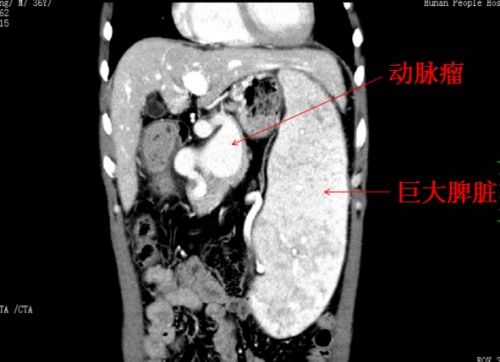

此外,王威的脾动脉上还有一个10×6×5cm3的巨大血管瘤,占据了腹腔一半位置,将胃后壁顶起,脾动脉起始部呈螺旋状扭曲,穿行在胰腺实质中,和扩张高压的门静脉、脾静脉紧密粘连,形成可怕的“血管峡谷”。瘤体随时都可能破裂出血,就像一个“不定时炸弹”,时刻威胁着患者的生命。

经过10个小时不间断努力,终于成功切除巨大脾动脉瘤,并同时完成“巨脾切除、门奇静脉断流术”,彻底解除了患者体内的这个“炸弹”,术中出血不到100毫升。